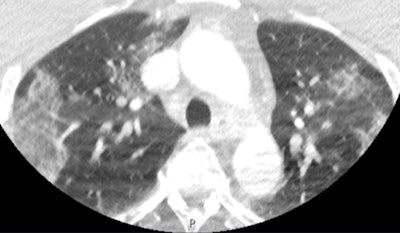

This scan shows apical ground-glass opacification in a patient with COVID-19. Despite the movement artifact that is not uncommon in acute stroke CT angiography, the biomarker is clearly present, alerting the treating team immediately that the patient has a high probability of COVID-19."This is particularly relevant given the limitations of currently available severe acute respiratory syndrome coronavirus 2 (SARS-CoV-2) reverse transcriptase polymerase chain reaction testing, as it takes time to complete the test and sometimes it is inaccurate," he noted.